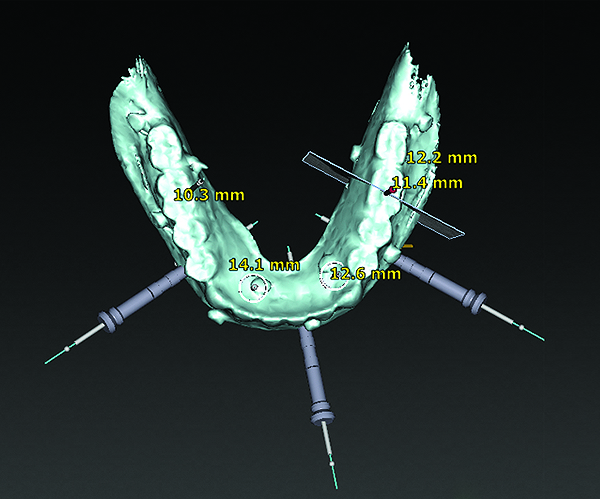

3D radiographic files (CT, CBCT) are stored digitally using a standardized digital imaging and communication in medicine (DICOM) format. In combination with a radiographic guide fabricated from a diagnostic wax-up, CBCT can be used to plan implant location and angulation based on prosthetically driven parameters and local bone/tissue constraints (Figure 8 through Figure 11). Currently, there are two different protocols to incorporate the radiographic guide in 3D scans and to perform computer guided surgery. The first is the double scan protocol, in which the patient wearing the radiographic guide and the radiographic guide alone are scanned separately. Fiduciary markers incorporated in the radiographic guide allow for matching of the two scans. This protocol allows for digitization of the surgical guide with great accuracy, irrespective of errors introduced by patient scans.18 Specialized software can be used to create a surgical guide (Figure 12).

3D radiographic scans obtained using the single scan protocol can be combined with digital mock-ups performed on intraoral optical scans or scans of casts,20 using the existing natural teeth as fiduciary markers. Different masks for bone, teeth, gingiva, and implants can be designated and processed (Figure 13 and Figure 14). This technology allows for greater accuracy, since implant position will be determined based on natural teeth (fiduciary markers) that are likely to be more stable and accurate than fiduciary markers placed on a radiographic guide.

(8) The use of CBCT and digital software for implant treatment planning. The radiographic guide in combination with a 3D CBCT was used to help plan implant position and location.

Figure 8

(9) The use of CBCT and digital software for implant treatment planning. The radiographic guide in combination with a 3D CBCT was used to help plan implant position and location.

Figure 9

(10) The use of CBCT and digital software for implant treatment planning. The radiographic guide in combination with a 3D CBCT was used to help plan implant position and location.

Figure 10

(11) The use of CBCT and digital software for implant treatment planning. The radiographic guide in combination with a 3D CBCT was used to help plan implant position and location.

Figure 11

(12) An example of a surgical guide produced using digital design and digital planning of implant position using the double scan protocol.

Figure 12

(13) An optical scan of patient’s teeth and diagnostic wax-up was combined with CBCT to facilitate treatment planning of implant placement. Note that there is a need for sinus augmentation to accommodate a dental implant on the right image (blue: tooth contours determined from wax-up/optical impression, red: soft tissue outline).

Figure 13

(14) An optical scan of patient’s teeth and diagnostic wax-up was combined with CBCT to facilitate treatment planning of implant placement. Note that there is a need for sinus augmentation to accommodate a dental implant on the right image (blue: tooth contours determined from wax-up/optical impression, red: soft tissue outline).

Figure 14